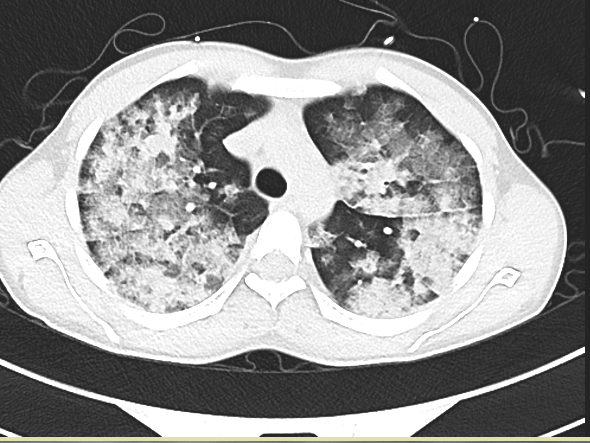

接诊医生在对小辉完善系列检查后发现:小辉血氧饱和波动仅有49%至60%(在不吸氧的条件下,正常血氧饱和度为95%以上),血压为89/63毫米汞柱(血压单位),脉率达每分钟144次,呼吸每分钟39次,双肺满布大量湿啰音,情况危急,随时会有生命危险。接诊医生立即联系了心血管内科,将小辉送至心血管内科接受紧急救治。

大附院心血管内科医师凭着丰富的临床经验,考虑小辉患的是急性肺水肿中极严重的急性高原肺水肿。小辉的病情随时有迅速恶化的风险,一旦得不到有效的救治,小辉即将面临昏迷甚至死亡!他们当即为小辉施行了系列紧急治疗。经过心血管内科医护人员齐心协力的救治后,小辉生命体征逐渐平稳,氧饱恢复到95%。

据大理大学第一附属医院院长、心血管内科专家吴新华介绍,急性高原肺水肿是一种急性致命性非心源性肺水肿,也是严重高原病最常见的类型。急性高原性肺水肿的主要症状表现为突发性胸闷、气喘、咳嗽、咳痰等,其发生机制主要为急性低氧引起肺动脉压力过度增高、肺血管通透性增高、肺水清除障碍、液体潴留及体液转运失调。如果该病能得到及时诊断和积极治疗,一般预后良好。解除病因、改善机体供氧是防治急性高原性肺水肿的首要措施,一旦延误诊断和治疗常可致死。(春城晚报-开屏新闻 记者刘文波 杨维琦 通讯员赵秋燕 大理大学第一附属医院供图)